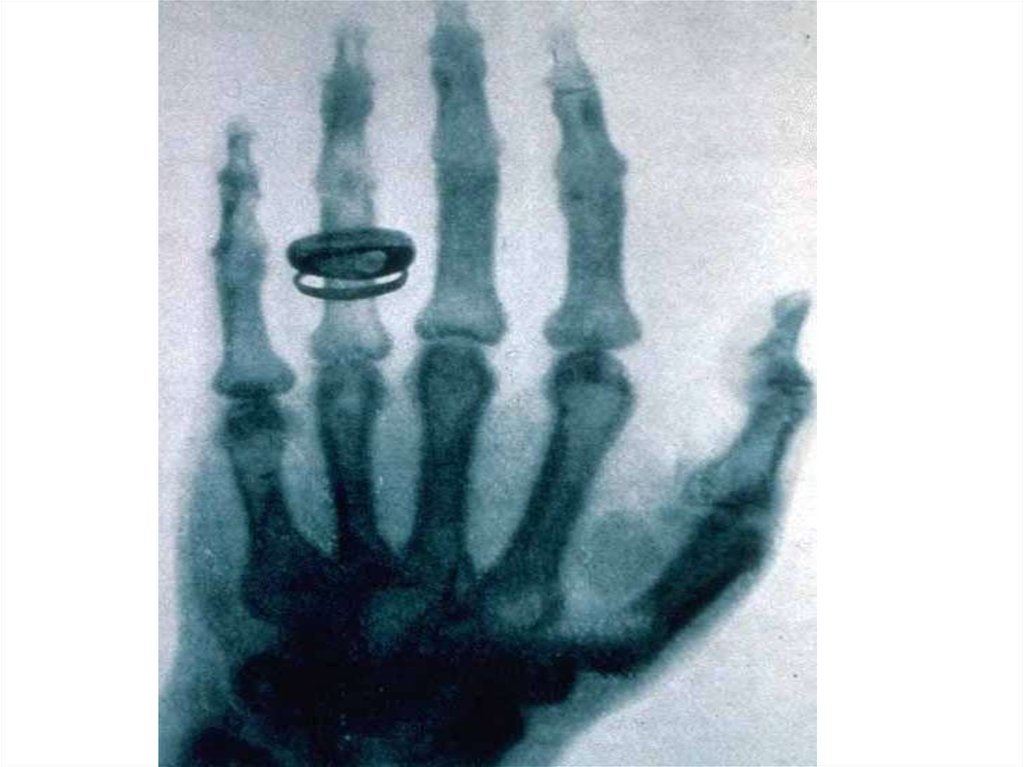

X-rays

1. X-ray